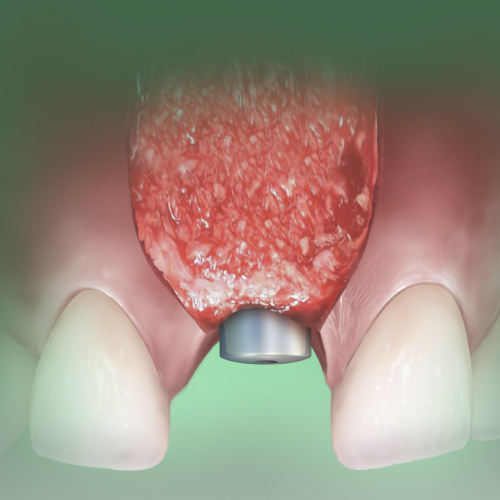

Implantology Updates

This Compendium eBook features a continuing education (CE) article on hard- and soft-tissue augmentation for implant therapy in the esthetic zone. This eBook also includes a case report article on a minimally invasive technique for the reconstruction of class III sockets with simultaneous i...

Implantology Advances

This Compendium eBook offers a continuing education (CE) article on partial extraction therapy in implant dentistry, with an emphasis on the biologic and anatomic conditions necessary for optimal outcomes with implant surgery. This eBook also includes a case report describing a strategy for...

Breakthroughs in Dental Implantology

This Compendium eBook offers a continuing education (CE) article on the treatment of retrograde peri-implantitis (RPI), a rare complication of implant placement that may interfere with implant survival. In addition, this eBook includes a case report on a novel approach for improving free gi...

Innovations in Implantology

This Compendium eBook offers a continuing education (CE) article that explores implant abutment and restoration design with respect to risk factors for peri-implant disease. A second article covers minimally invasive extraction site management with dehydrated deepithelialized human amnion/c...